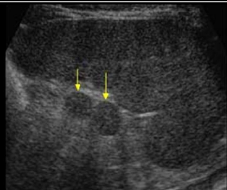

Identify this image.

Accessory spleen or splenule